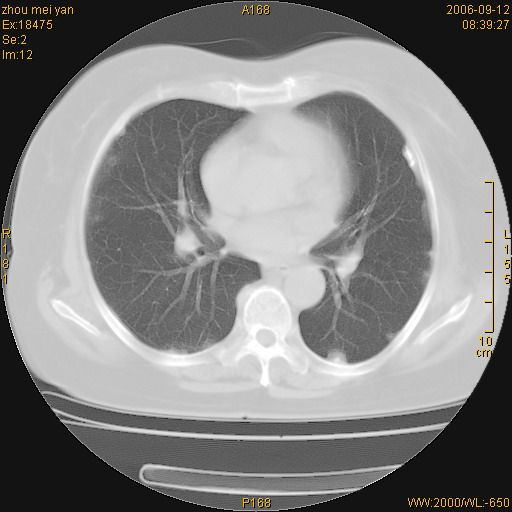

患者、女、55岁。因心率失常住院检查ct发现胸部多发结节。腹部b超肝、胆、胰、脾、肾、子宫附件未见异常。无结核病史,无粉尘接触史。请大家来会诊。谢谢!

病变位于胸膜,多发结节,边界清楚,内见小结节状钙化。其它未见异常。

双侧胸膜多发结节,形态不规则,边缘较清楚,每一个结节中心似乎都有钙化点的特征,与胸膜广基相切。临床无结核病史,无粉尘接触史。

影像表现十分有特点:双侧肋胸膜及膈胸膜广泛散在分布大小在2至6mm左右,较大病灶中心可见钙化。

考虑恶性胸膜间皮瘤可能性大,病灶位于胸膜,以宽基地与胸膜相连,呈结节样改变,部分病灶内可见点状钙化影。请各位老师多多指导!

双侧肋胸膜及膈胸膜广泛散在分布大小不等结节影,较大病灶中心可见钙化。